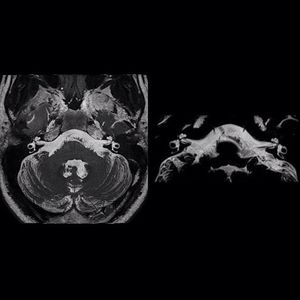

Reduced-FOV imaging for 3D TSE (#ZOOMit SPACE) uses dynamic excitation pulses to achieve selective field-of-view (zoomed) imaging, without aliasing artifacts. With this sequence we can achieve faster, higher-resolution imaging (due to higher SNR) and we can detect and evaluate smaller lesions, especially in areas prone to susceptibility artifacts. 3D SPACE of the inner ear, 47% reduction in imaging time in right image (ZOOMit SPACE). #MRI #3D_SPACE #new_MR_applications